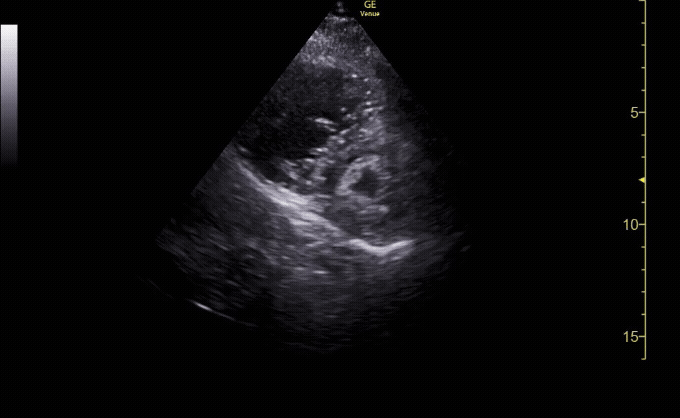

Apical 4 Chamber view with the left side of the heart on the right hand of the screen.

c/o Colleen Andrews, MD